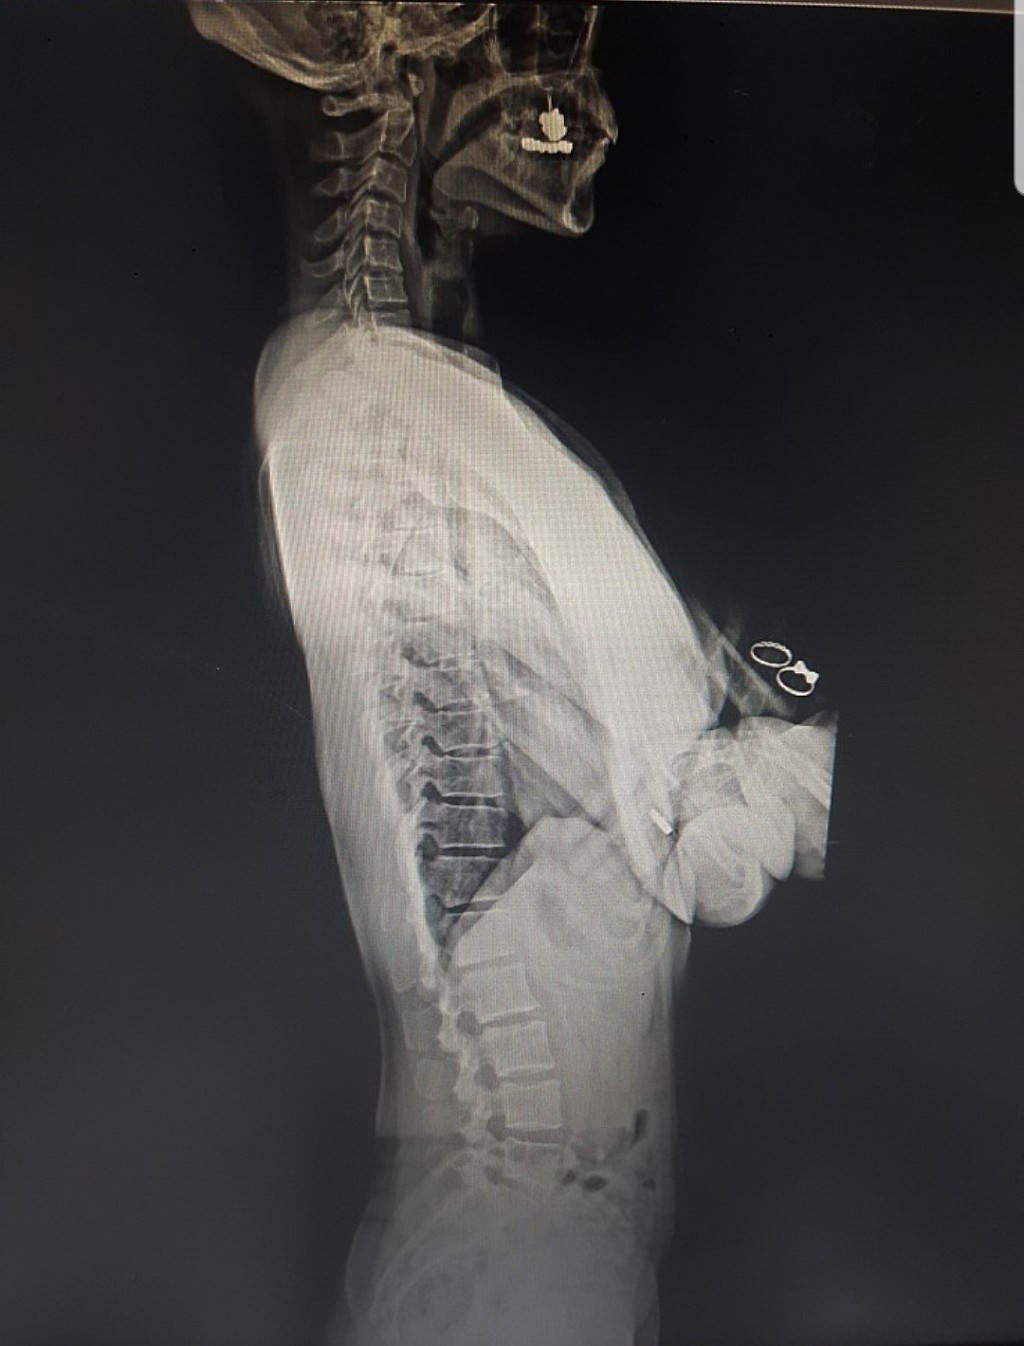

2018년 엑스레이 입니다

많이 아프지 않았냐. 우리병원에서 심한 척추측만을 제외하고 척추심각하기로는 탑3안에 든다 라고 하시더라구요.

엑스레이는 2018년의 경추와 수련전 엑스레이 촬영으로 경추를 비교한 것 입니다. 다른 수련한거 없었고 그저. 웨이브베게 베고 자기만했어요 그래서 눈에띄게 큰변화는없지만 , 역 C가 미세하게🤏 일자가 되어가는게 보입니다. 지도자 과정중에는 수련못하면 C무브만이라도 했었고 그래서인지 요즘은 롤러를 베고 잘수있게 되었어요👏 또한 휴대폰 왠만큼해도 머리 아프지않구요. 등이 아픈건 완전히 다 나은건아니지만 앞으로 남은 숙제라고 생각하고 꾸준히 할 예정입니다. 등이 부드러워지는 그날까지!